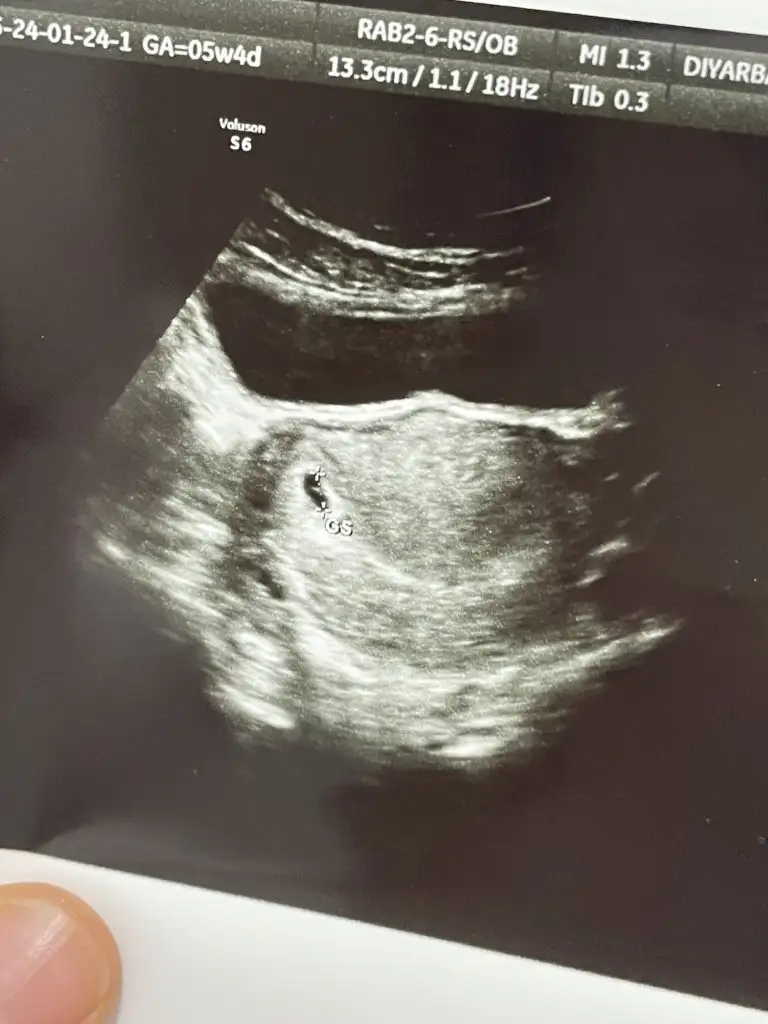

Sat 4 aralık civarı olan hamişler nasıl gidiyor, benim hafif arka yanlarım ağrıyor, sol üst bacağımın etleri ağrıyor , kasığımda mı karnımda mı bilmiyorum bi ağrı var ama adet sancısı gibi değil. Mide bulantısı var. Üşütmekten mi acaba